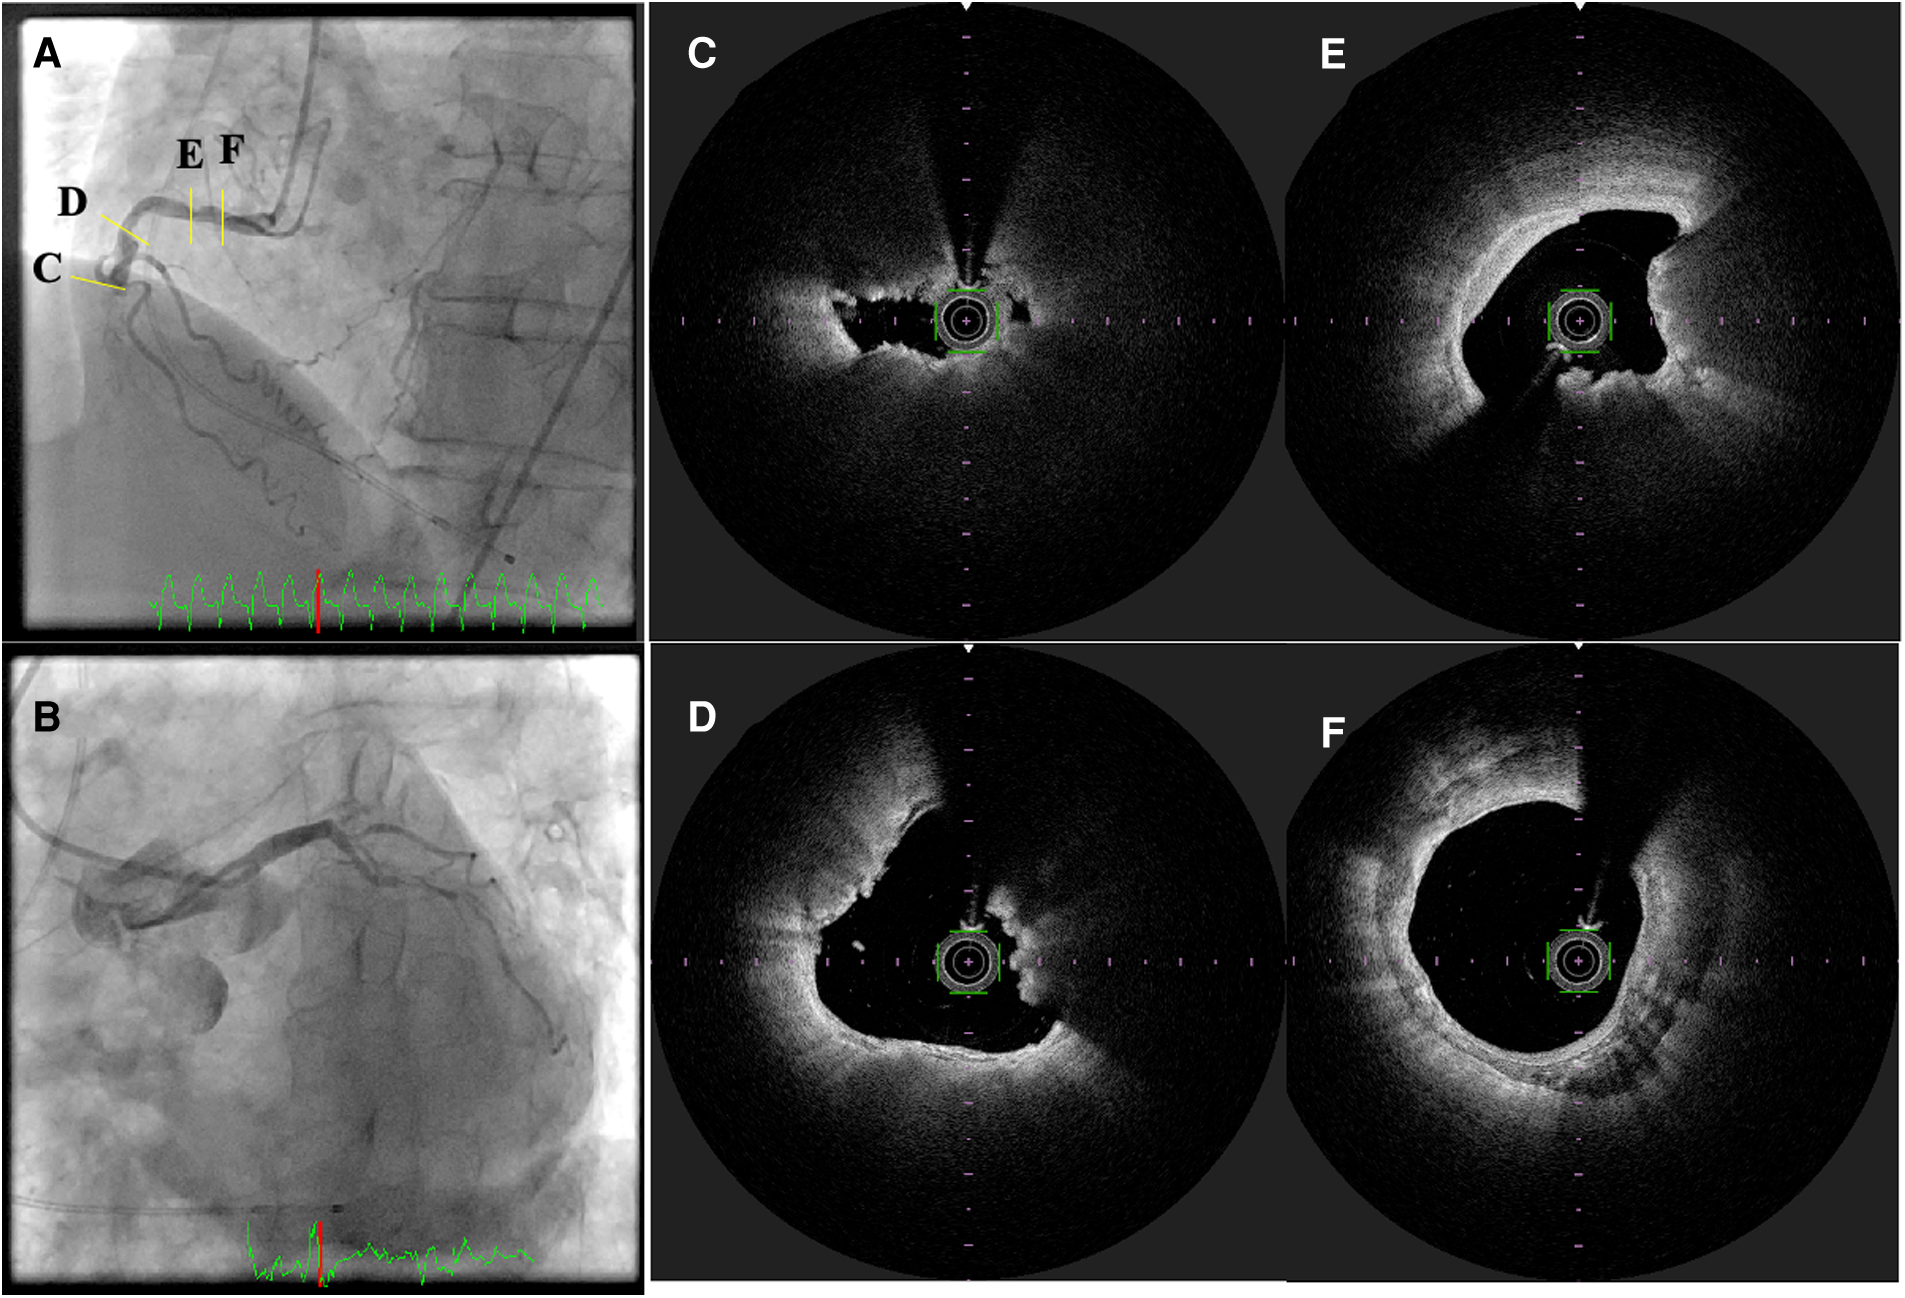

Figure 4

Optical frequency domain imaging of ST-segment elevation myocardial infarction. (A,B) Invasive coronary angiography revealed total occlusion of the mid-portion of the right coronary artery with collateral flow to the left descending coronary artery. (C–F) optical frequency domain imaging (OFDI) images after thrombectomy. (C) Thin capped fibroatheroma, (D,E) calcified nodules (yellow arrows), and (F) calcification.